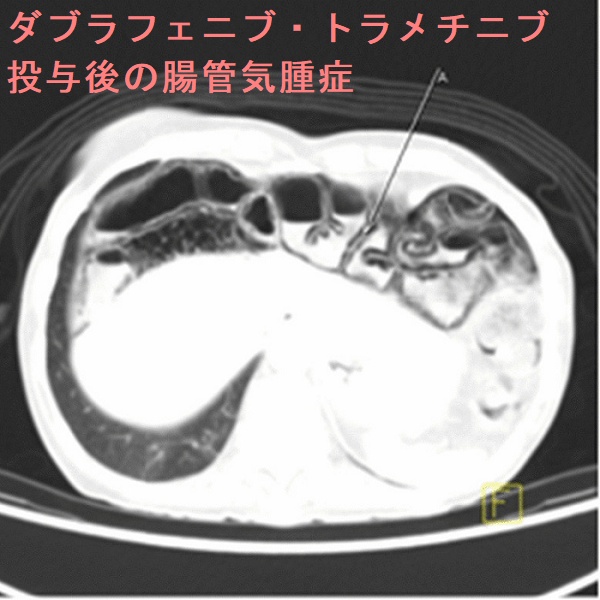

腸管気腫症(pneumatosis intestinalis)とは、大腸壁や小腸壁の粘膜下層・漿膜下層にガスが溜まり、気腫(空気嚢胞)を形成する病態。原因として、約15%は特発性ですが、約85%は続発性で、

分子標的薬(チロシンキナーゼ阻害薬) ベバシズマブ(アバスチン®)[甲状腺機能低下症も併発]、スニチニブ、レンバチニブ[J Med Case Rep. 2021 Nov 12;15(1):556.]、ダブラフェニブ・トラメチニブ[J Med Case Rep. 2021 Mar 2;15(1):109.];腸壁への血流障害

甲状腺乳頭癌肺・骨転移に対するダブラフェニブ・トラメチニブ投与後4カ月で見つかった腸管気腫症[J Med Case Rep. 2021 Mar 2;15(1):109.]

腸管気腫症は、無症状で自然軽快することが多い。腹痛・血便を伴う場合は絶食や酸素投与、手術切除。